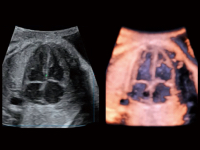

豐富的血流動(dòng)力學(xué)檢測(cè)技術(shù),可在不同醫(yī)療場(chǎng)景中高效捕捉血流信號(hào),助力臨床診療。

在傳統(tǒng)血流的基礎(chǔ)上優(yōu)化掃查和算法策略,能夠更好的抑制組織信息,提煉紅細(xì)胞運(yùn)動(dòng)信息,得到更高幀頻,高靈敏度和分辨率的血流信號(hào),還原更真實(shí)的血流動(dòng)力學(xué)。

通過(guò)創(chuàng)新的Matrix E自適應(yīng)濾波算法,能有效濾除軟組織和噪聲信號(hào),最大限度保留超低速微細(xì)血流的信號(hào);結(jié)合超長(zhǎng)時(shí)間域算法,極大提升細(xì)微血流的敏感性和空間分辨率,更真實(shí)的反應(yīng)組織、包塊的血流灌注情況。